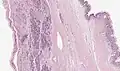

Microscopy

Mucinous cystadenoma of the pancreas -